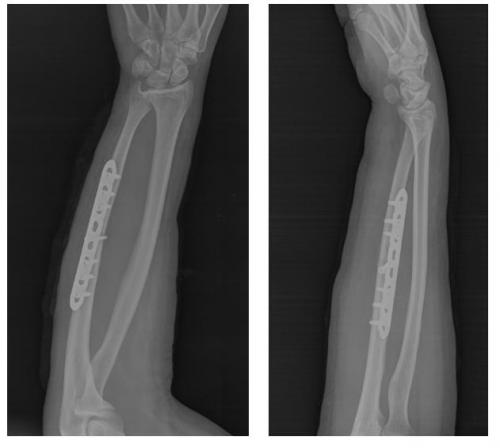

В настоящее время для остеосинтеза простых (поперечных и косых) переломов костей предплечья чаще всего используются различные модификации пластин с компрессирующими и блокируемыми отверстиями. Ниже мы рассмотрим методику выполнения остеосинтеза простого косого перелома локтевой кости при помощи пластины с угловой стабильностью 3,5 мм Synthes на 8 отверстий, кортикальных и блокируемых винтов.

В случае простых переломов, где линия перелома образована 2 основными крупными фрагментами (возможно наличие небольшого количества мелких фрагментов не препятсвующих стабильной фиксации) выполняется остеосинтез при помощи пластины и винтов с достижением максимальной механической стабильности в зоне перелома и компрессии между собой отломков.

Такой остеосинтез был впервые предложен и претерпел дальнейшее широкое распространение благодаря международному сообществу травматологов – ортопедов AO\ASIF.

На рентгенограммах после операции остеосинтез выглядит так.

Такой остеосинтез крайне надёжен и позволяет давать полную амплитуду движений непосредственно сразу после операции. С целью заживления послеоперационной раны и минимизации боли в раннем послеоперационном периоде (первые 2 недели после операци) рекомендуется ношение косыночной повязки и использование грелки со льдом местно по 20-30 минут до 5 раз в день.

После снятия швов можно использовать руку для бытовых нужд. Через 6 недель выполняется рентгенконтроль, при наличии признаков сращения нагрузка увеличивается до полной. Однако форсированные физические нагрузки противопоказаны до 3 месяцев после операции.